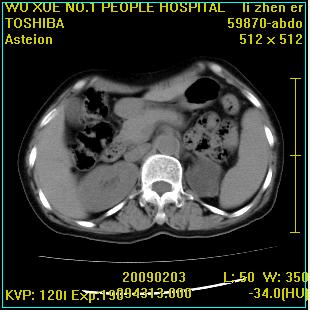

标题: CT18564:女,57岁,无不适,体验B超提示肾积水等 [打印本页]

标题: CT18564:女,57岁,无不适,体验B超提示肾积水等

左侧多囊肾可能。

左肾及左输尿管上端结石,左肾重度积水并左肾萎缩(不排除左肾先天性发育不良)。

左输尿管上端结石,左发育不良性多囊肾并积水;

右肾代偿性增大并肾盂积水,脾大。

此患都左肾呈囊性变,边缘有高密度钙化,还是考虑结核吧.